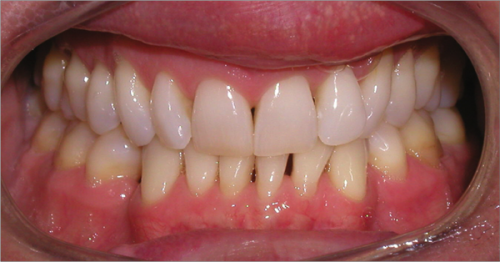

44 year old female:

Diagnosis:

- Upper and lower arch collapse due to missing teeth

- Retrusive angulation of upper & lower front teeth

- Severe collision and wear of front teeth

Treatment:

- Combination of Invisalign and braces

- Creating space for placement of an implant in the lower arch

- 28 months